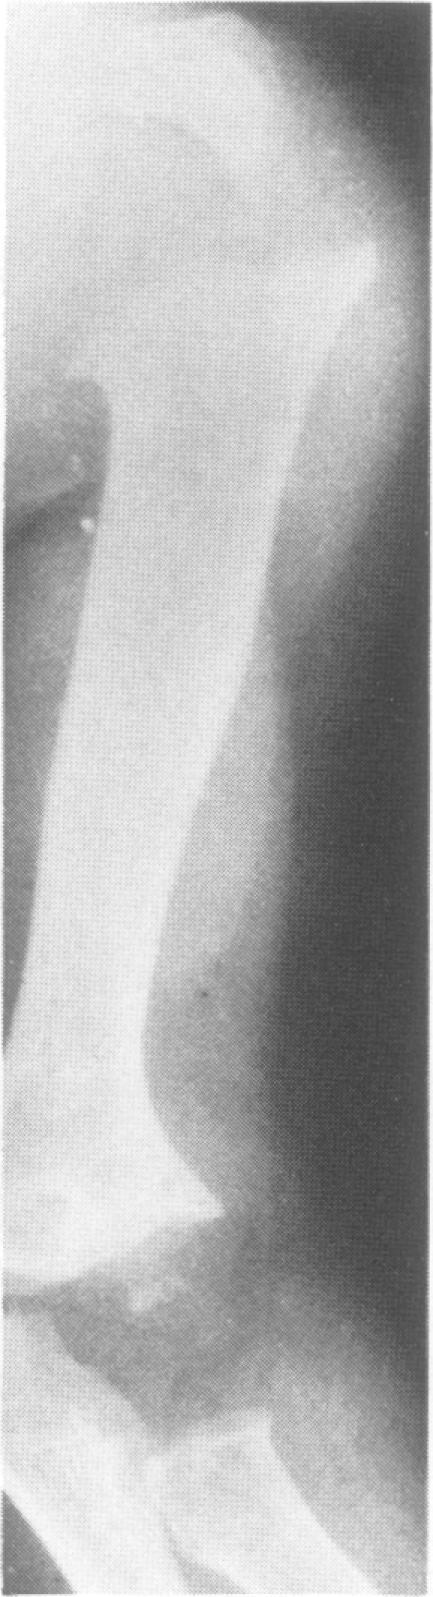

This survey reviews the diagnosis (predominantly radiological) of 32 cases of pseudoachondroplasia from 26 kindreds and illustrates the natural history and varying appearance of the disordered bone growth from infancy to adult life. In addition, an attempt has been made to detect phenotypic differences between autosomal dominant and recessive types (excluding isolated cases), analysing 10 kindreds of dominant inheritance (three in the current survey, seven from published reports) and six of recessive inheritance (three in the current survey, three from published reports). There appears to be no clinical or radiographical feature which clearly distinguishes them, but, using height as a criterion of severity, among those with autosomal recessive inheritance there was a disproportionate number of the most severely affected cases and there also appears to be very little intrafamilial variation. It is possible that pseudoachondroplasia can be subdivided into autosomal dominant mild and severe and autosomal recessive mild and severe, but full delineation must await elucidation of the basic defect at biochemical and molecular levels.

本调查回顾了来自26个家族的32例假软骨发育不全病例的诊断(主要是放射学诊断),并阐述了该疾病从婴儿期到成年期骨骼生长紊乱的自然病史及不同表现。此外,还尝试检测常染色体显性和隐性类型(不包括散发病例)之间的表型差异,分析了10个显性遗传家族(本次调查中有3个,已发表报告中有7个)和6个隐性遗传家族(本次调查中有3个,已发表报告中有3个)。似乎没有能明确区分它们的临床或影像学特征,但是,以身高作为严重程度的标准,在常染色体隐性遗传患者中,受影响最严重的病例比例过高,而且家族内差异似乎也很小。假软骨发育不全有可能可细分为常染色体显性轻度和重度以及常染色体隐性轻度和重度,但要进行全面分类,必须等待在生化和分子水平上阐明其基本缺陷。